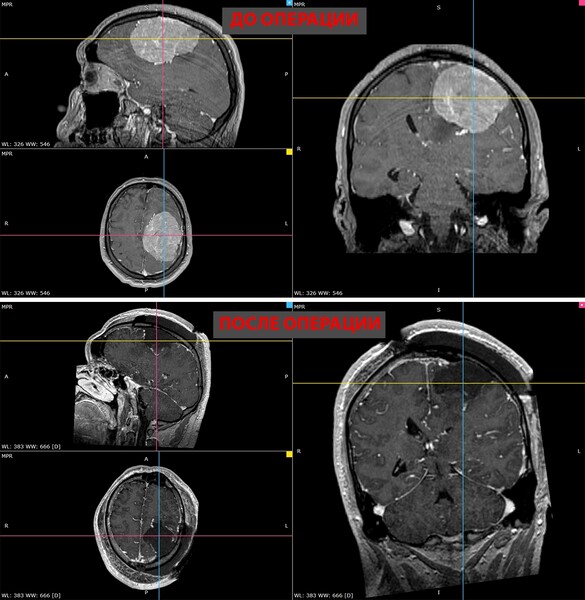

В ноябре прошлого года у мужчины появилась слабость в правой руке и затруднения речи — МРТ выявила у него менингиому диаметром более восьми сантиметров в левом полушарии мозга. К концу года рука практически перестала работать, ходьба давалась пациенту с трудом.

Пятичасовая операция прошла успешно. Опухоль удалили полностью. Уже на следующий день появились движения в руке, через две недели пациент снова стал сам ходить. У него восстановились речь и движения, приступы исчезли.